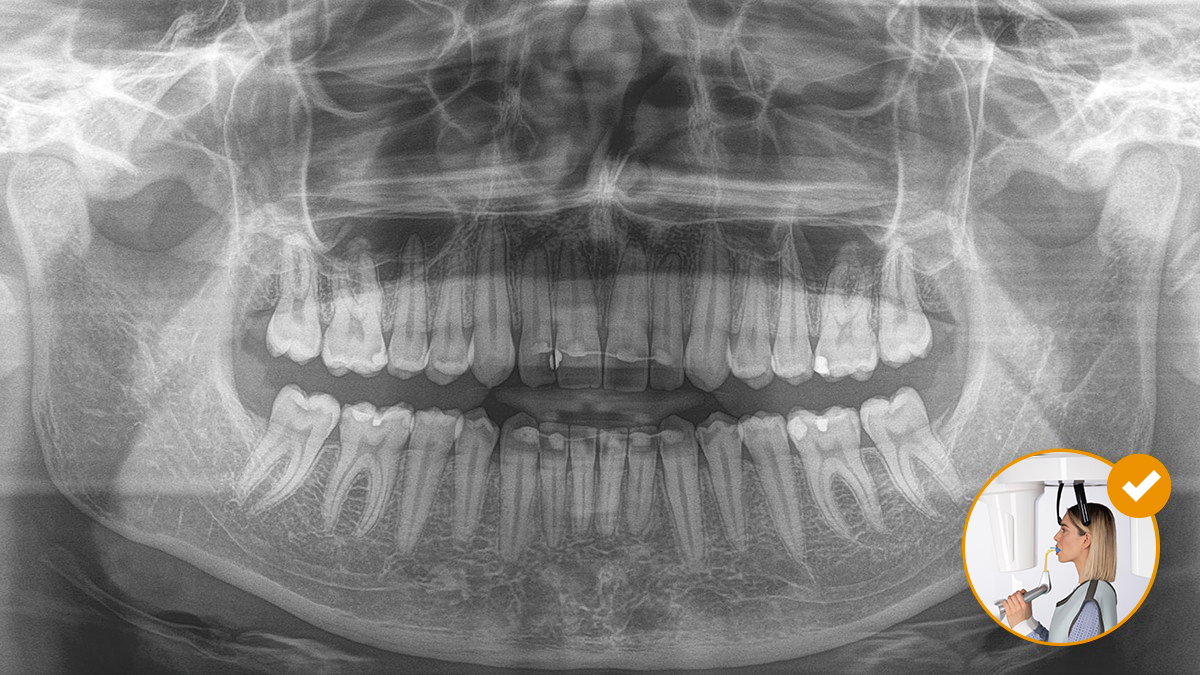

El resultado: Escaneos precisos gracias al bloque de mordida oclusal